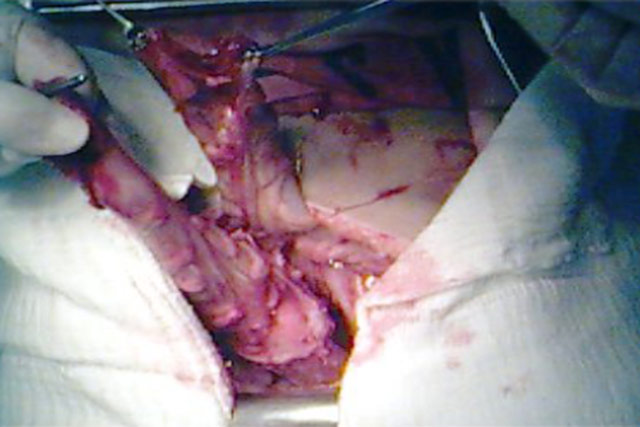

Presença do tumor dissecado.

Outro angulo do tumor dissecado,

vemos inferiormente o reto livre.